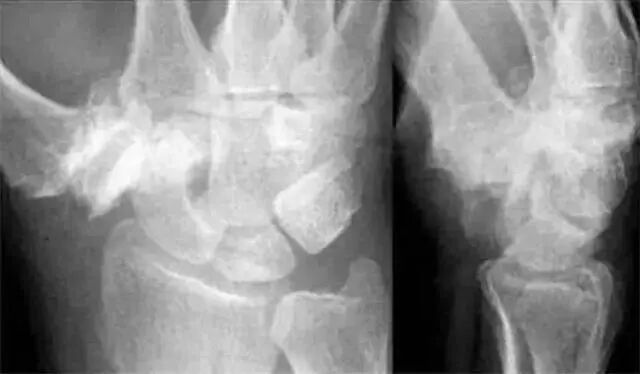

Analyze-腕骨弧线正位弧线不连续,侧位明显脱位。

1.月骨-三角骨间隙不平行,存在重叠。

2.钩状骨和月骨也存在重叠。

3.桡骨、月骨、舟骨近极和头状骨近极平行关系存在。

4.三角骨、钩骨、头状骨远极、大多角骨和舟骨远极平行关系也存在。

5.头状骨和舟骨骨折。

诊断:经舟骨、经头状骨月骨周围骨折-脱位。